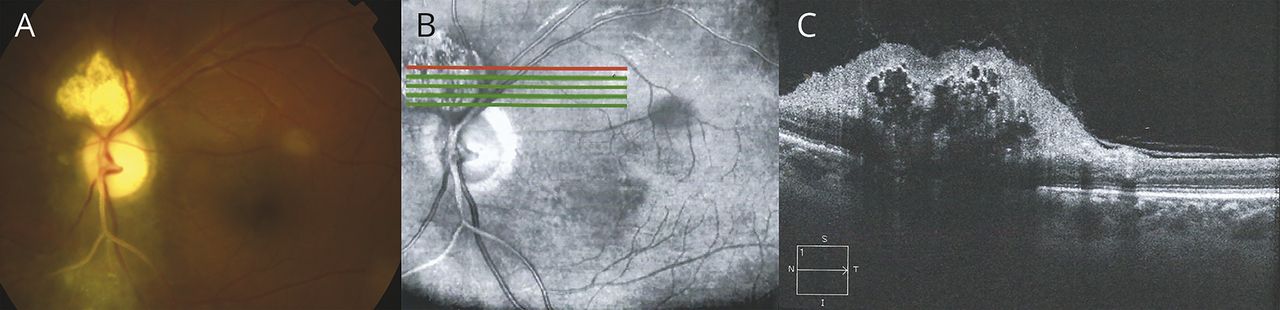

图1

眼底镜检查和光学相干断层扫描(OCT)

10月左眼眼底镜检查(A)和(B, C)显示损伤与破坏intralesional囊肿,位于边界上的左视神经和视网膜错构瘤兼容。